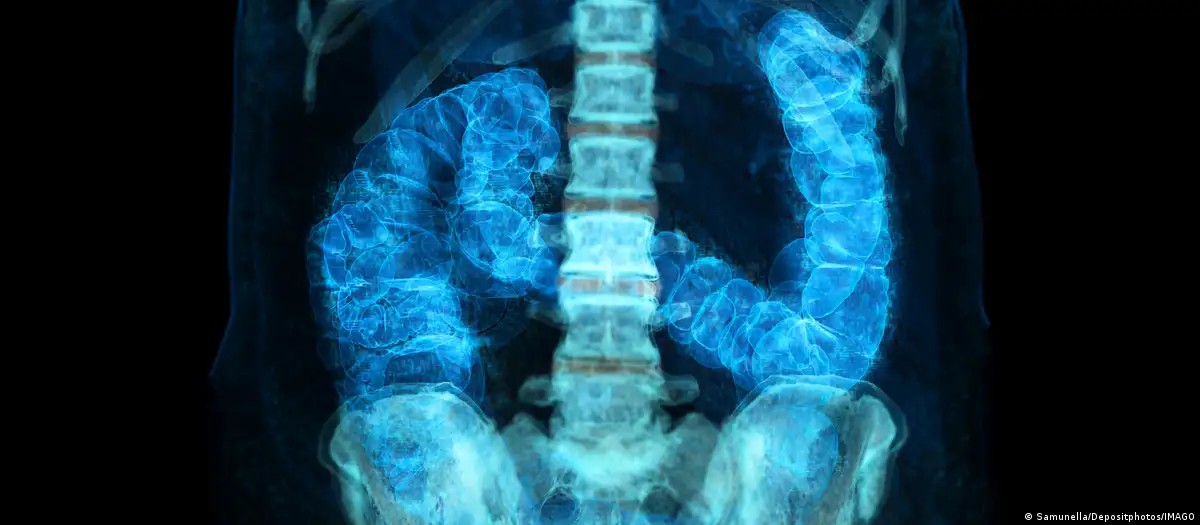

Incidência aumenta entre menores de 50 anos, e especialistas buscam respostas para o avanço precoce da doença. No Brasil, mortes devem crescer 36% até 2040.O câncer colorretal, antes associado sobretudo a adultos mais velhos, avança cada vez mais entre homens e mulheres jovens. Nos Estados Unidos, já é a neoplasia que mais mata abaixo dos 50 anos.

Além disso, o local onde o tumor aparece ao longo do cólon, que tem formato semelhante a um ponto de interrogação, começando de um lado do abdômen, curvando‑se para o outro e terminando no reto, influencia sua agressividade e o tratamento.